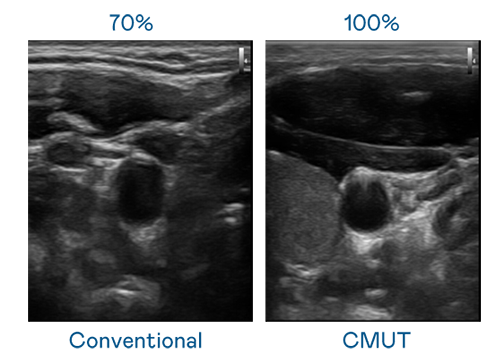

CMUT 技术是一种用电容式微机电元件来产生超音波讯号的技术。与传统 PZT 压电式技术相比,CMUT 频宽增加 30%,更宽频的超音波讯号让影像解析度大幅提升,是实现高影像品质医疗超音波扫描、促进精准医疗发展的关键技术。

大频宽带来超清晰影像

超音波影像的解析度高低,首先取决于探头能发出的讯号频宽。乐天使 CMUT 可提供高清晰的超音波讯号,提供高频宽、高灵敏度、影像纹理细节更高的超音波影像,协助医护人员缩短影像判读时间及利用精准的医疗影像进行诊断。